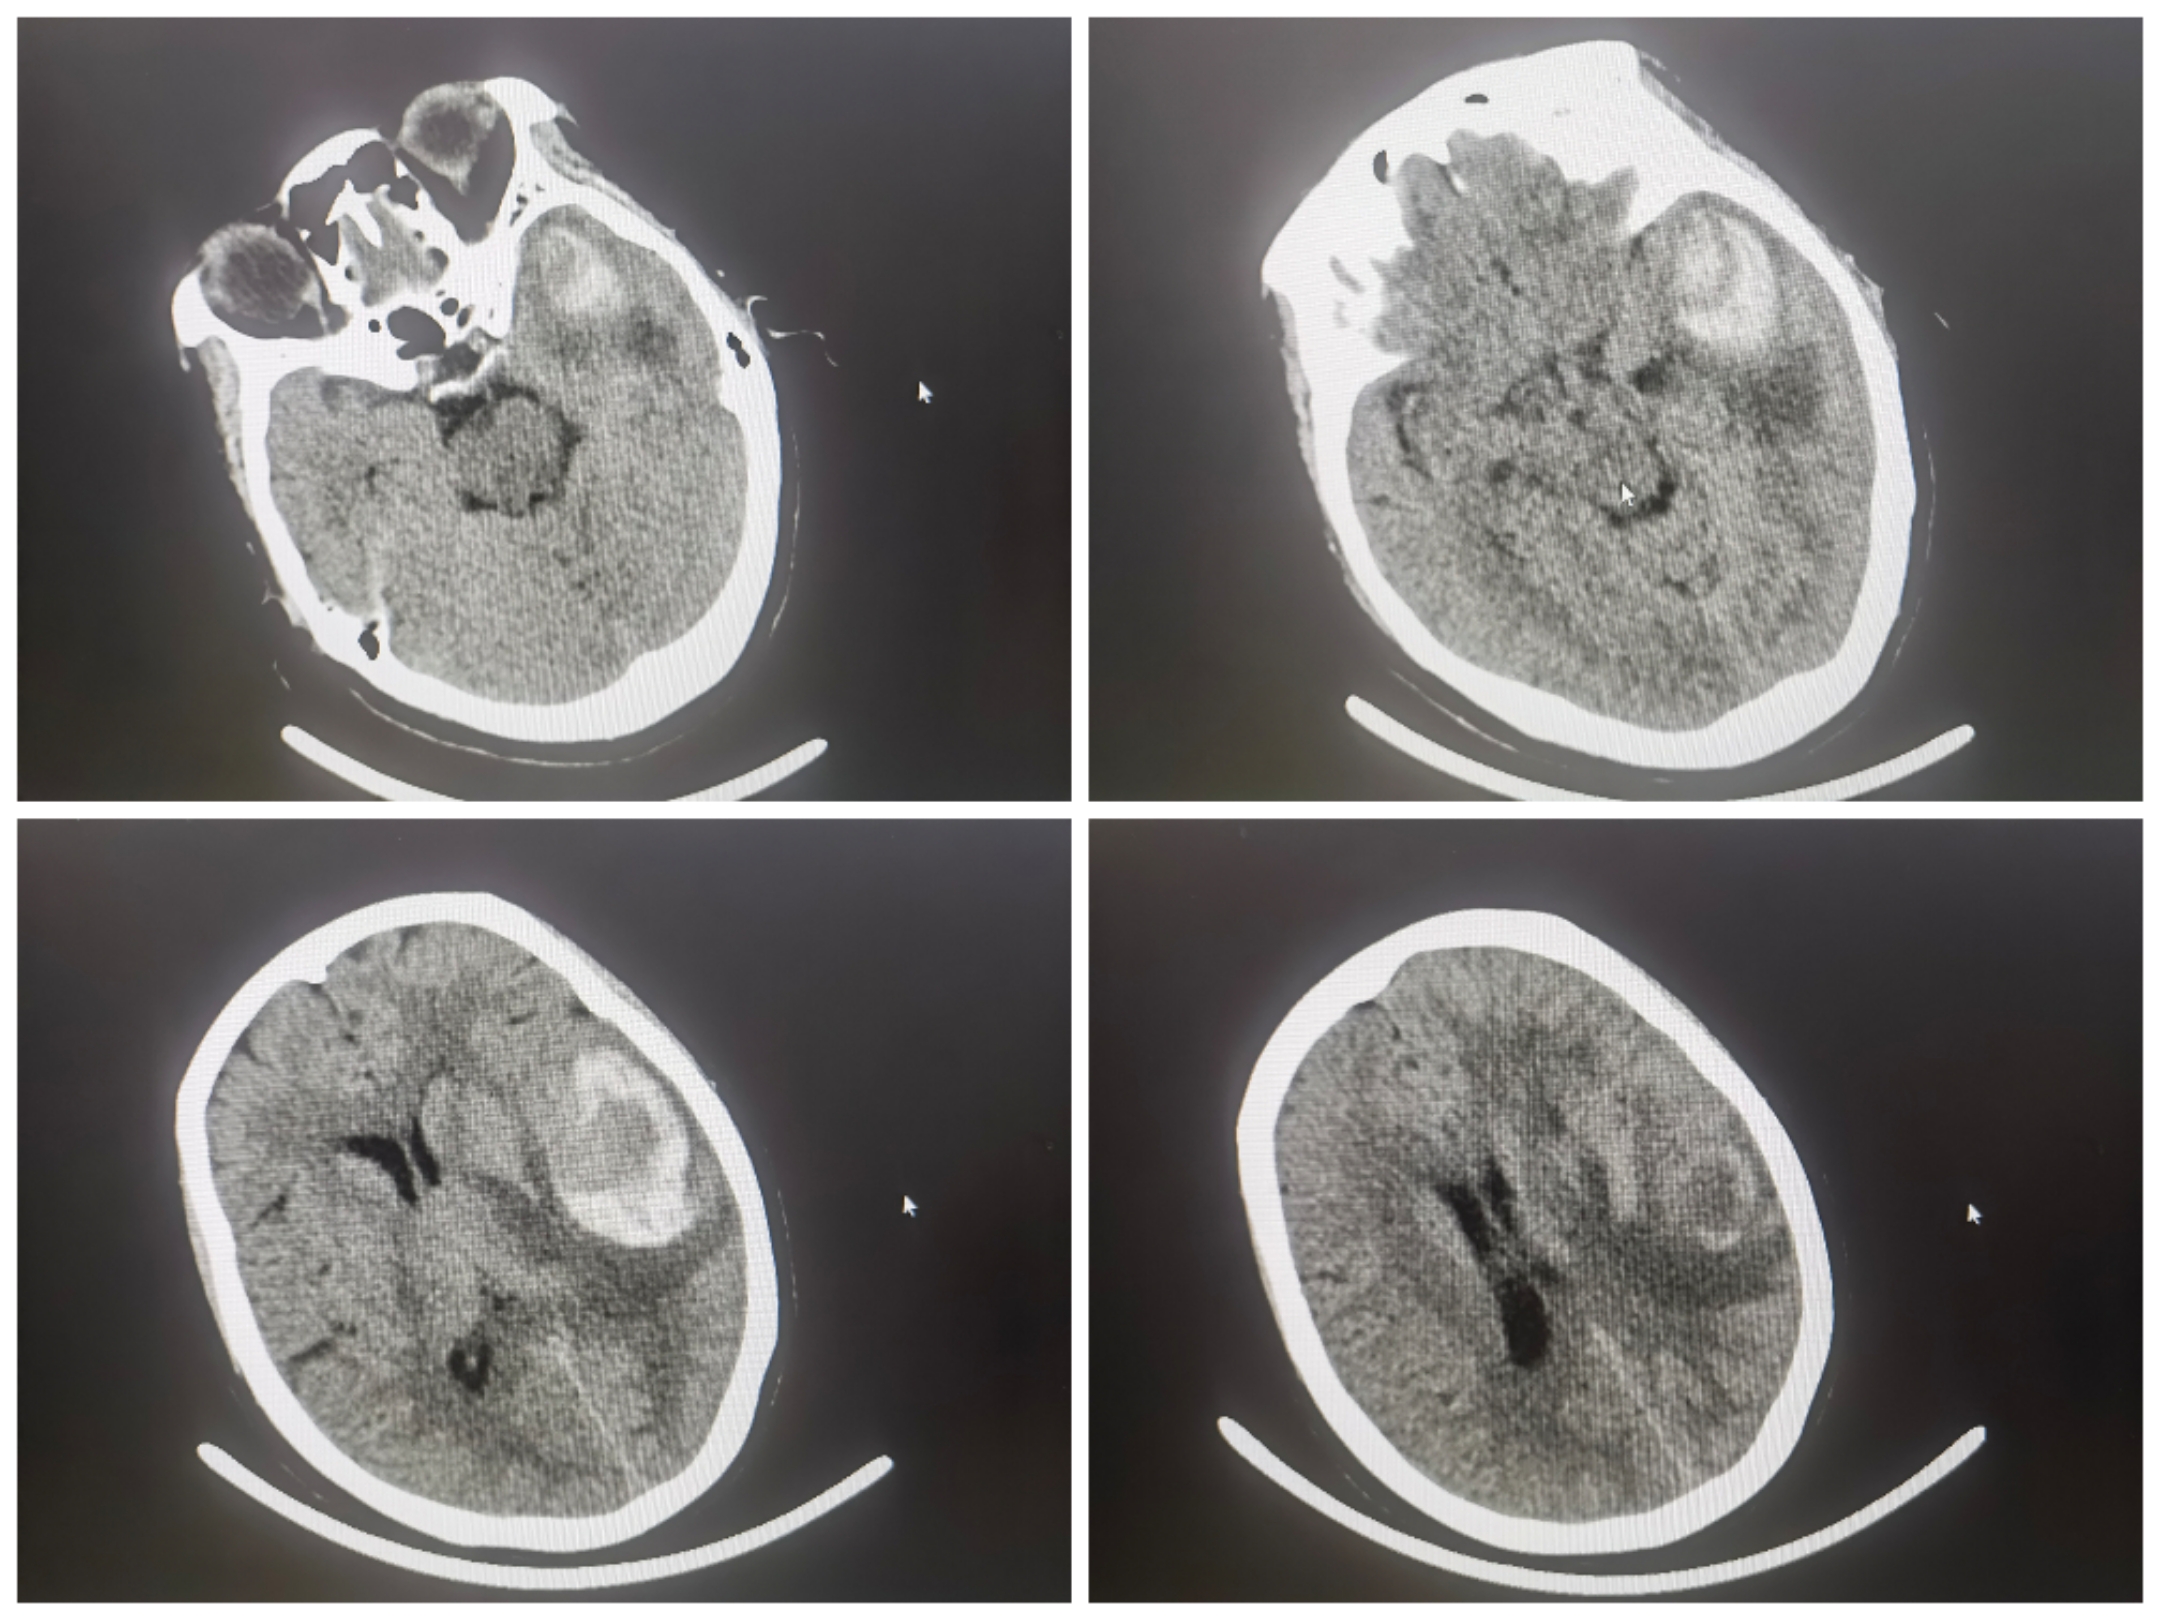

患者头疼1周余入院,CT提示左侧颞叶血肿,入院神智嗜睡,GCS14分,四肢肌力正常

因头疼1周余就诊,行头颅CT提示左侧颞叶血肿,CTA提示左侧大脑中动脉瘤。神智嗜睡,GCS13-14分,首选开颅血肿清除+夹闭动脉瘤。患者家属反复拒绝开颅。

术前造影

术前3D情况

手术计划:三系统,支架导管放置上干,双微管栓塞

工作位,支架导管+双微导管到位情况

栓塞过程:双微管分区栓塞

栓塞术后情况

栓塞术后3D重建